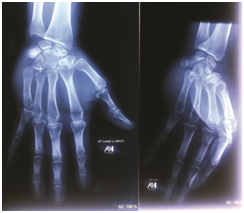

A 35 years young man admitted into orthopaedics department of our hospital with severe pain and swelling of right hand after blow to a hard object. He was unable to move right little finger and also painful movement of other fingers. Clinically there was a depression in the dorsomedial aspect of right carpus proximally and swelling rest of the hand. The little finger was abducted and extension in position. Some shortening of fifth digital ray. There was no sign of neuro-vascular injury. Radiographs of right hand with wrist joint was done. Antero-posterior and lateral view of x-ray, the base of fifth metacarpal was displaced proximally. Phalanges of little finger abducted in antero-posterior view. There was also palmar displacement of fifth metacarpal base in lateral view. There was no other displacement or fracture of carpals, metacarpals and phalanges of right hand. So, isolated palmar dislocation of fifth carpometacarpal joint (right) confirmed by radiographs.

Figure 1 Preoperarive Radiographic view of AP & Oblique.